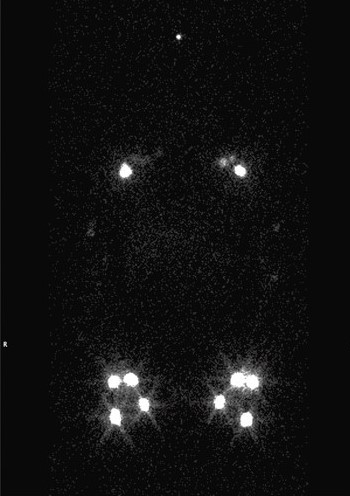

lymphoscintigraphy

SPECT CT

SPECT/CT Lymphoscintigraphy:  SPECT/CT stands for single-photon-emission computed tomography. This scan consists of combining a CT scan (which lets us see your anatomy clearly) with a scan that tracks the progression of a tracer through that anatomy over a certain period of time. It lets us see the volunteer's anatomy with clarity as the tracer moves through.